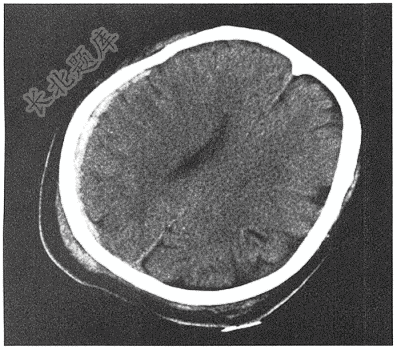

- 单项选择题男性,25岁,外伤2小时( )

A、脑出血、头皮血肿

B、脑挫裂伤、头皮血肿

C、蛛网膜下腔出血、头皮血肿

D、硬膜下出血、头皮血肿

E、硬膜外出血、头皮血肿